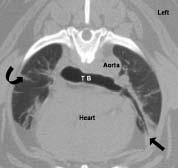

Computed tomographic image of a dog with pulmonary fibrosis at the level of the tracheal bifurcation (TB).There is fibrosed lung tissue in the ventral parts of the lungs (straight arrow) and fibrin scars originating from the pleural surface (curved arrow).A main goal of the clinical study is to determine characteristic computed tomographic findings of pulmonary fibrosis.